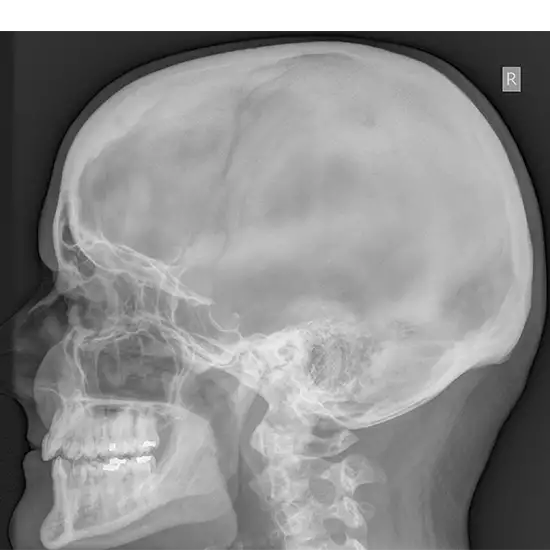

Mastoid refers to the temporal bone of the skull lying behind the ear. This bone features air-filled open spaces. When there is an infection in the middle ear, this region is afflicted by a disease called mastoiditis. The oblique view X-ray examination examines the mastoid bone from a lateral perspective.

The x-ray oblique view exam provides valuable mastoid information. It gives the following mastoid pathology results:

* Determining the cortical bone's width

demonstrating the symmetry of both mastoids

Determining whether or not the mastoid cavity is preserved

The creation of cholesteatoma is explained (abnormal skin growth in the middle ear behind the eardrum)